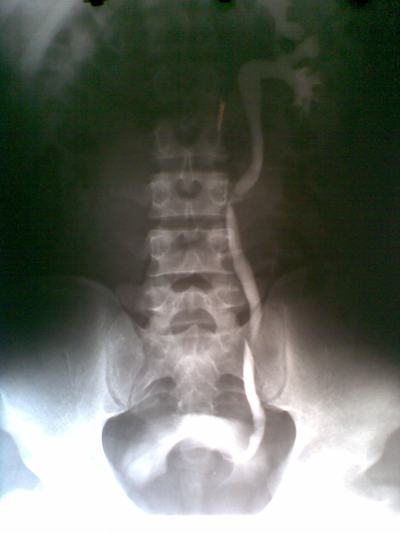

Kết quả siêu âm niệu qua thành bụng: thận phải có kích thước 6x8cm, thận trái bình thường. Tại cổ bàng quang có khối bề mặt nhắn, kích thước 6x5cm.

Kết quả UIV cho thấy trên phim 15 đến 180 phút thận trái bình thường (đường bài niệu giãn nhẹ do ép bóng tại niệu quản đoạn dưới), thận phải không ngấm thuốc cản quang. Bàng quang có khối choán chỗ (xin xem hình).